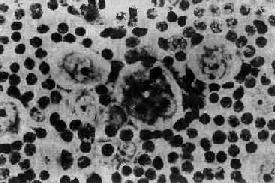

镜下,淋巴结的正常结构破坏消失,由瘤组织取代。瘤组织内的细胞成分多样,有些是肿瘤成分,有些是非肿瘤成分。瘤组织中有一种独特的多核瘤巨细胞,体积大,直径约15~45μm,椭圆形或不规则形;胞浆丰富,双色性或呈嗜酸性;核大,可为双核或多核,染色质常沿核膜聚集成堆,核膜厚。核内有一大的嗜酸性核仁,直径约3~4μm,周围有一透明晕。这种细胞称为Reed-Sternberg细胞(R-S细胞)。双核的R-S细胞的两核并列,都有大的嗜酸性核仁,形似镜中之影故称镜影细胞(图11-1)。这些双核和多核的R-S细胞是诊断HD的重要依据。

图11-1 何杰金病示镜影细胞